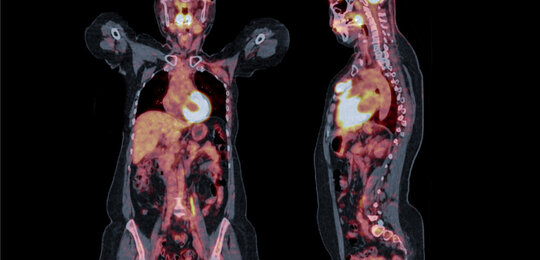

Enabling a quantitative approach to cardiovascular disease diagnostics

Over a third of all deaths in the EU are caused by disorders of the heart or blood vessels collectively described as cardiovascular disease (CVD), making it the leading cause of mortality. As well as the significant social toll, CVD is also estimated to cost the EU economy around €210 billion a year. The current ‘gold standard’...